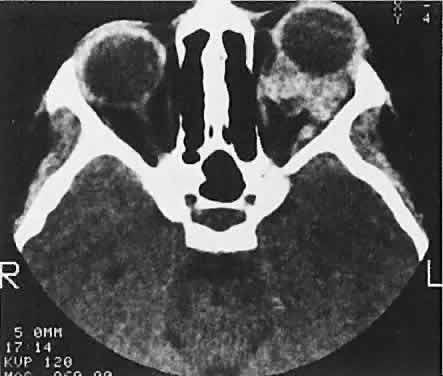

In cases of suspected neuroblastoma metastatic to the orbit, the primary tumor may be shown by abdominal or thoracic imaging studies. A histologic diagnosis generally is required, however. Orbital soft tissue involvement usually follows extension from bony metastasis (Fig. 3). Therefore, orbital biopsies should be performed extraperiosteally, because the periorbita may still be intact and constitute a relative barrier to tumor extension. Because the histologic differential diagnosis includes other poorly differentiated tumors of childhood, speci-mens should be fixed in both formalin and glutaraldehyde, and fresh tissue also should be submitted.

Fig. 3. A large metastatic focus of neuroblastoma has destroyed the body of the sphenoid bone and has extended into both orbital apices. A second site involves the outer portion of the right sphenoid wing and extends into the orbit and the middle cranial and temporal fossas. The tumor originated in the right adrenal gland.

Sporadic North American cases have a less-definitive viral association. These patients differ clinically in their age of presentation (mean, 11 years) and in the usual site of tumor origin (intra-abdominal lymphoid tissue).40,41 Involvement of the facial bones and orbit is less common in the North American cases, but invasion of the orbit from the sinuses may occur42,43 (Fig. 4).

Fig. 4. Burkitt's lymphoma involving the posterior ethmoids, skull base, and both orbital apices in a 5-year-old boy.